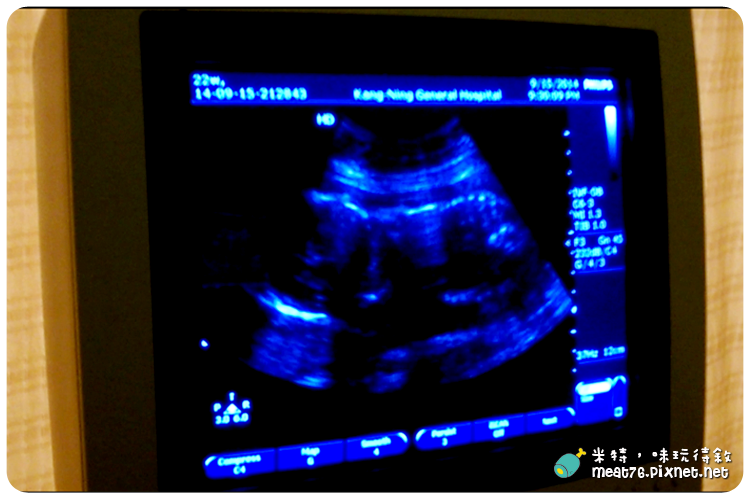

之前看朋友分享產檢時拍的影片,

所以這次心血來潮也想來記錄一下畫面,

結果醫生說太遲了啦,現在連他都看不清楚寶寶的樣子了,

真是令人難過,

所以想要產檢的時候把超音波影音拍下的準爸媽們記得請在一開始跟大約20週前的產檢做這件事,

寶寶再長大一點就會擠在一起,連超音波照片也看不太清楚 ╮(╯◇╰)╭